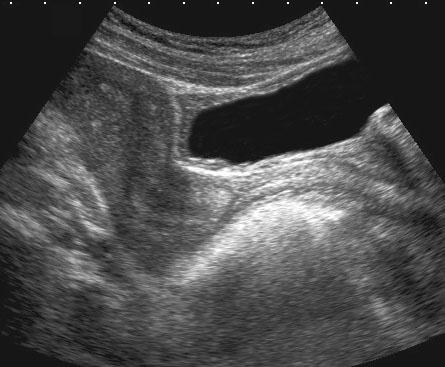

Phát hiện tình cờ “polyp bàng quang” (mũi tên) trên CT ở bệnh nhân nữ trẻ.

Xác nhận cấu trúc dạng polyp dẹt (mũi tên) bằng siêu âm bụng.

Nội soi bàng quang hoàn toàn bình thường, cho thấy khối được phủ bởi niêm mạc bàng quang bình thường.

TVUS chứng minh khối thực chất là một ổ lạc nội mạc tử cung và cho thấy bờ tăng âm (*) của tử cung bị mờ, gợi ý xâm lấn khu trú.

TVUS cũng phát hiện DIE trong túi cùng Douglas (không hiển thị ở đây).